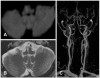

Background: The medial vestibulospinal tract (MVST), which descends in the medial longitudinal fasciculus (MLF), may mediate the vestibular evoked myogenic potentials (VEMPs) in the contracting sternocleidomastoid muscle. We report herein abnormal VEMPs in a patient with medial medullary infarction (MMI) that appeared to involve the MLF.

Case report: A patient with infarction involving the right medial medulla showed decreased p13-n23 amplitude and increased p13/n23 latencies of the VEMPs on the right side. These abnormal VEMPs recorded in an MMI patient support the theory that VEMPs are mediated by the MVST contained within the MLF.